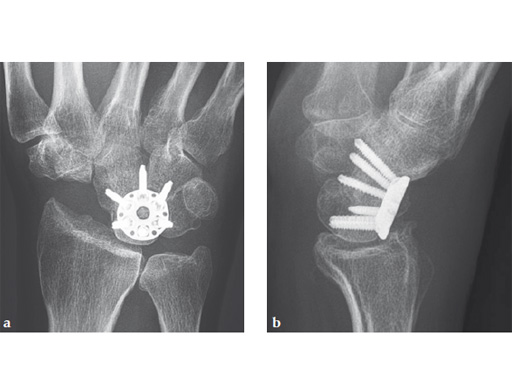

Fig 1ab Preoperative x-rays. Note the carpal collapse a a b nd DISI deformity.